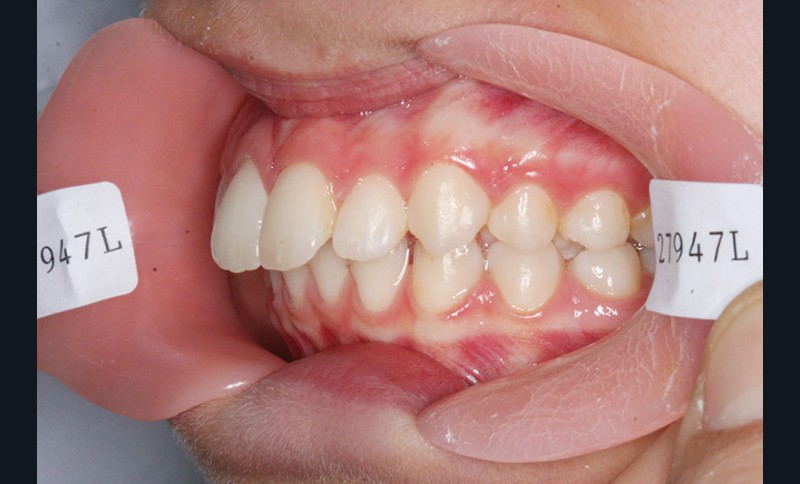

Nous sommes en présence d’une patiente adolescente âgée de 12 ans ½ dans une phase de croissance faciale favorable.

Elle présente une classe II squelettique par rétrognathie mandibulaire et une classe II dentaire molaire et canine droite et gauche associée à une biproalvéolie incisive maxillaire et mandibulaire.

L’environnement vertical est normodivergent.

Le pronostic de correction de la classe II est favorable mais il est très important de souligner la vestibuloversion incisive mandibulaire et le risque parodontal associé (fig. 1 à 3).